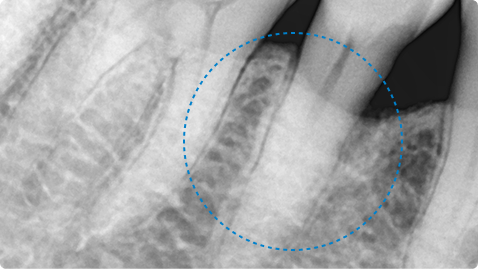

오랜 잇몸병으로 발치 직전의 치아, 잇몸 재생 치료로 자연치아 유지

치료 전

치료 후

치료 내용

• 좁고 깊은 치주낭(잇몸 주머니), 염증과 치아 흔들림, 타 치과에서 발치 권유

• 치주수술 + 엠도게인 적용으로 잇몸과 잇몸뼈 재생 유도

• 치료 후 치주낭 깊이 감소, 잇몸 회복 및 흔들림 안정